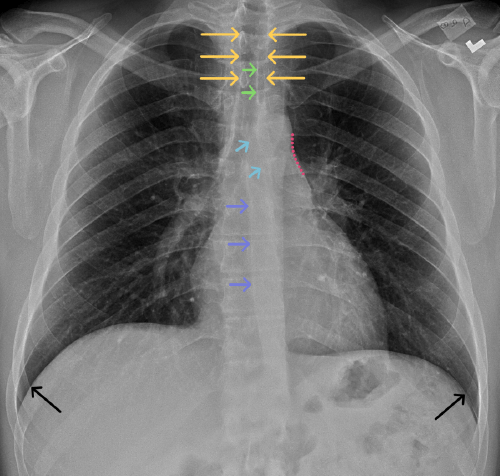

Chest

Chest

Chest radiograph & CT anatomy

Chest

Chest

Chest radiograph & CT anatomy